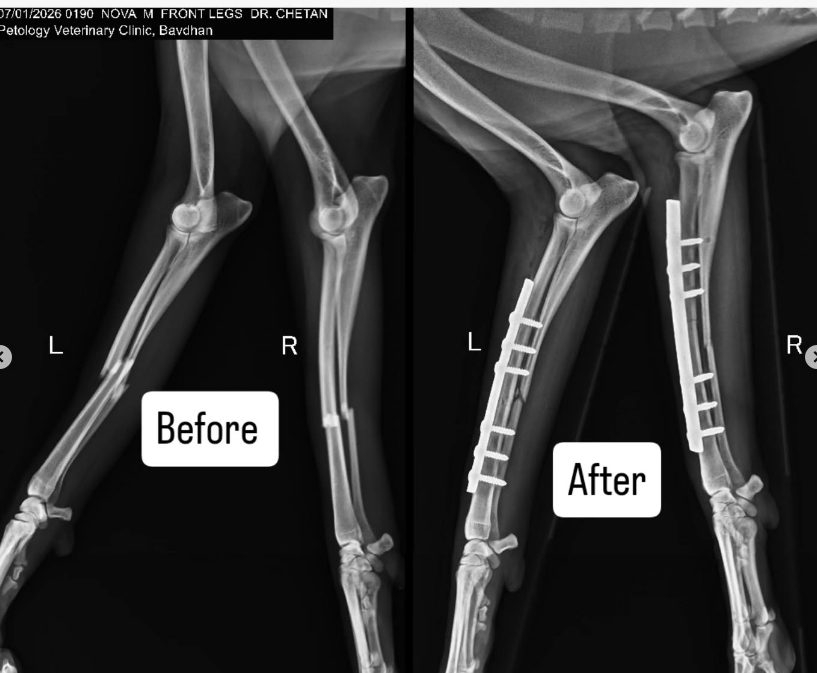

The surgery has cost us Rs 25,000 per leg. It’s a double whammy in Nova’s case as whoever drove over him literally broke BOTH his front legs into two!!

You can see the BEFORE and AFTER of the xrays in the slides above and also the estimate sheet of the costs involved.